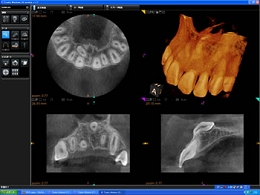

コーンビームCT

・患者様に安心安全なCT

CTとはコンピューター断層撮影装置のことですが、歯の中や骨の中を立体的に撮影し診断を行うための機器です。

インプラント治療はもとより、歯周病の診断、歯の破折、歯内療法における根管の形状や根尖の確認、埋伏歯の位置確認、外科的処置時の動脈や神経の走行状態の診断など、その応用範囲は大変大きく、様々な分野の診査診断において非常に威力を発揮します。

通常の歯科用コーンビームCTは一度に大きな部分を撮影するため、最低でも20秒~40秒以上の撮影時間が必要となるため、被曝線量がどうしても大きくなってしまいます。

当院の歯科用コーンビームCTは顎全体を1/3ずつ分割して撮影することが可能なため、11秒で撮影を完了することができます。このことにより、必要とする部位以外に不必要なX腺を照射する必要がなくなるとともに、被曝腺量を極めて少量に抑えることが可能になります。

現在アメリカなどでは過剰なCT検査による、発癌リスク上昇の危険性が指摘されおりますが、CT大国と言われる日本でも被曝線量を今後十分に考慮する必要があると考えております。